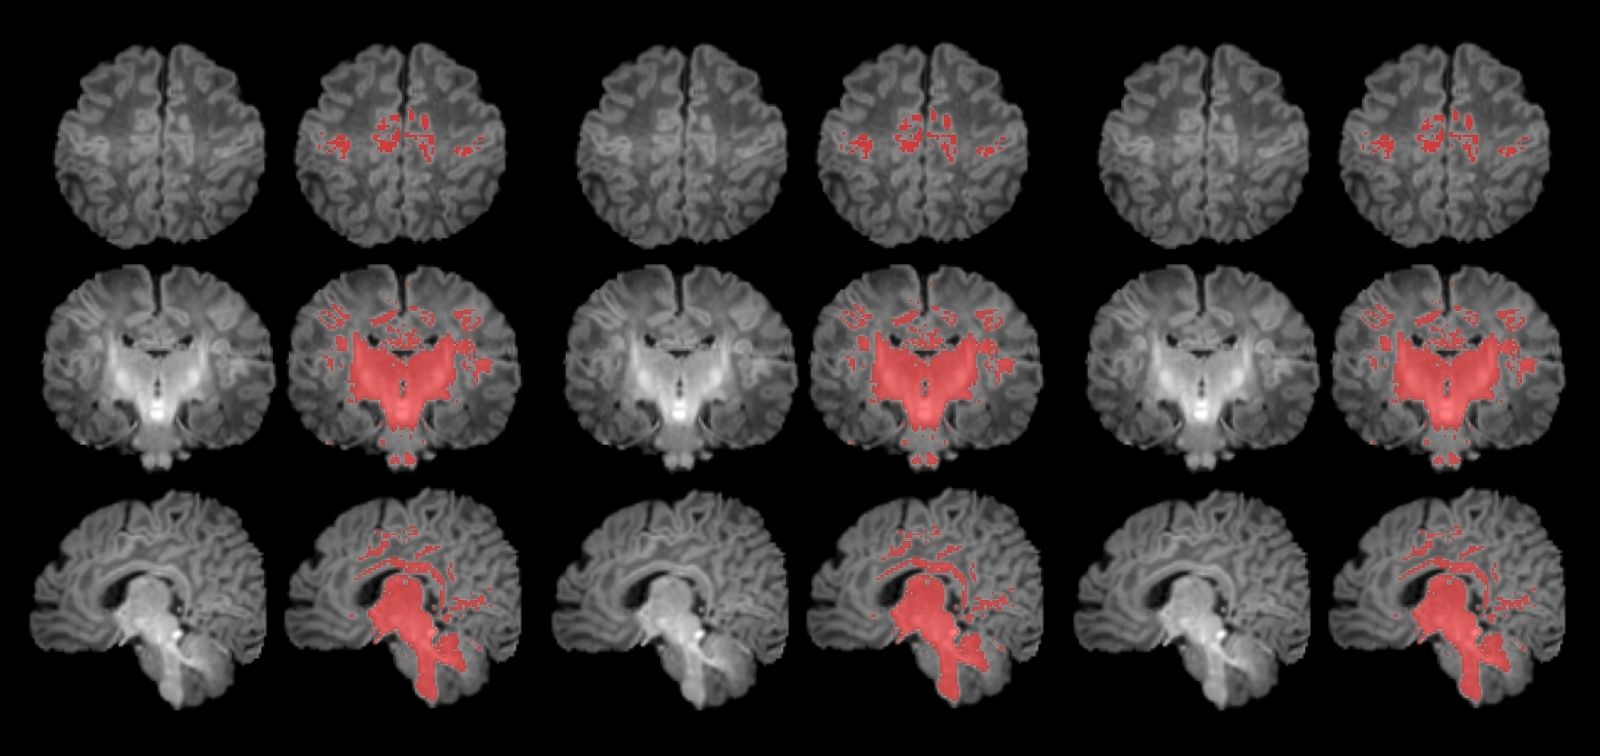

Para llevar a cabo el estudio se reclutó a mujeres embarazadas en seguimiento en el Hospital Clínic Barcelona, el Hospital de Sant Pau y el Hospital Sant Joan de Déu. Se monitorizaron los niveles de contaminantes atmosféricos a los cuales estaban expuestos durante la gestación y, después del parto, se seleccionó a 132 recién nacidos. A estos se les realizó una resonancia magnética antes de cumplir el primer mes de vida para observar el grado de maduración cerebral según sus niveles de mielinización.

Los resultados muestran una correlación clara entre una mayor exposición materna a PM2.5 durante el embarazo y una menor mielinización en el cerebro de los recién nacidos. “La contaminación atmosférica, concretamente las PM2.5, se asocia con una alteración en el proceso de mielinización, un mecanismo esencial de maduración cerebral. Por ello hay que continuar controlando la contaminación y estudiar cómo esta ralentización puede influir en el desarrollo posterior del cerebro de los niños y niñas”, expresa Martínez-Vilavella. El trabajo también indica que este efecto responde a la combinación de los diferentes elementos que forman las PM2.5, sin que se pueda identificar un único elemento como responsable.